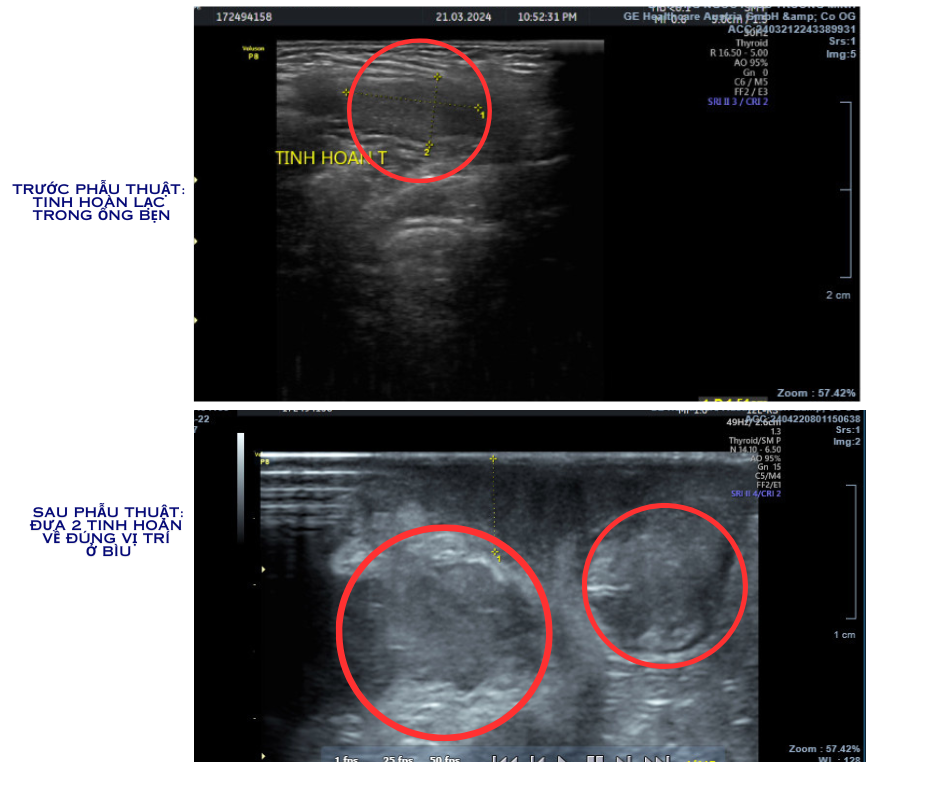

Chị Bùi Thảo - là mẹ của Q.K (2 tuổi, Hà Nội) từng phẫu thuật hạ tinh hoàn tại Bệnh viện Đa khoa Hồng Ngọc - chia sẻ: “Con tôi được phát hiện bị hạ tinh hoàn ẩn cả 2 bên lúc gần 2 tuổi, cũng được xem là khá muộn. Tôi đã rất lo lắng khi nghe giải thích về nguy cơ nếu điều trị muộn. Thật may các bác sĩ bệnh viện Hồng Ngọc đã phẫu thuật thành công, chỉ trong 1 lần mổ đưa tinh hoàn 2 bên của con về đúng vị trí. Kết quả kiểm tra sau phẫu thuật của con bình thường, 1 ngày sau mổ con đã ăn và đi lại được.”

Hình ảnh siêu âm trước và sau khi được phẫu thuật hạ tinh hoàn